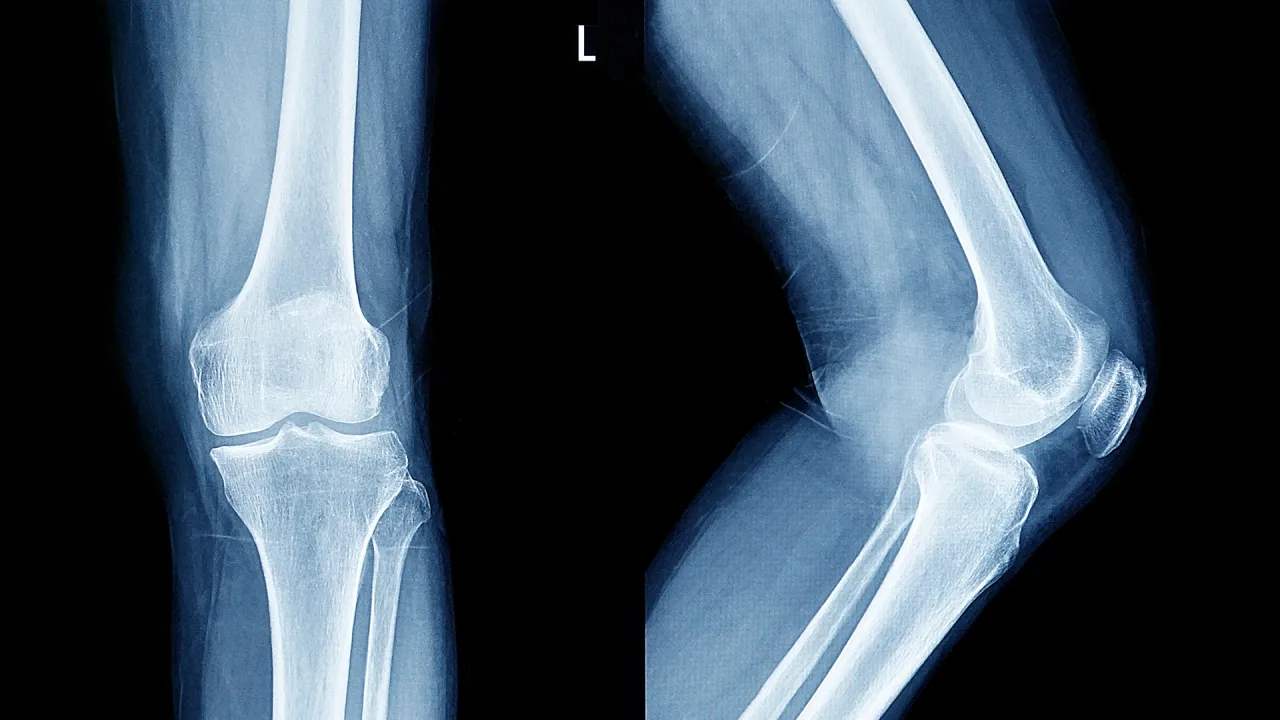

Scientist identifies a critical age stage where bones begin to lose their hardness

Khaberni  - Hasmik Jasmine Samvelian, the first lecturer in Biomedical Science at Anglia Ruskin University in the UK, stated that bones begin to lose their hardness gradually in most people after the age of 25-30.

According to her, bone disintegration and renewal processes remain balanced in young people. Bone mass usually peaks between the ages of 25 and 30, and thereafter, bone destruction becomes more common gradually, leading to a decrease in bone density over time.

Ageing is considered a major risk factor, but there are a number of additional factors that may accelerate this process. Hormonal changes, in particular, play a significant role. A decrease in estrogen levels after menopause leads to an increase in bone loss, causing fractures in nearly half of the women over fifty.